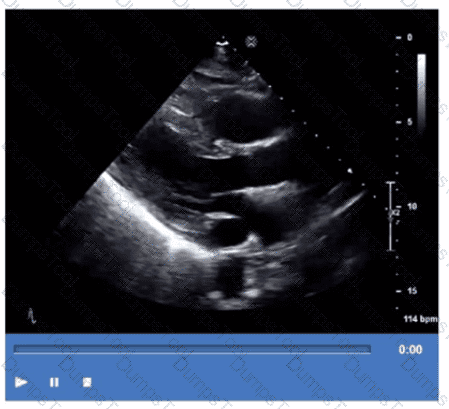

Which step is next in further evaluation of the abnormality shown in this video?